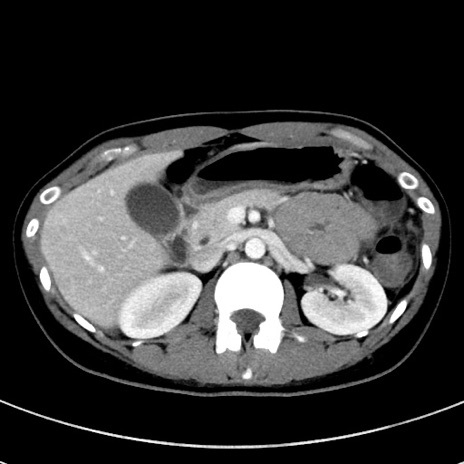

冠状断像

【症例】20歳代女性

【主訴】嘔吐、下腹部痛

【現病歴】昨日夕食後に嘔吐し下腹部痛が出現。本日になっても嘔吐持続し改善しないため来院。

【身体所見】意識清明、BT 37.2℃、BP 108/67mmHg、腹部:平坦、やや硬、下腹部正中から右にかけて圧痛あり、反跳痛軽度あり、tapping pain(+)。

【データ】WBC 13600、CRP 14.94